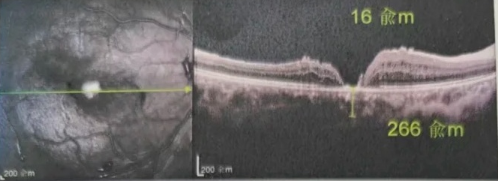

最讓吳爺爺難以置信的是:術(shù)后只需保持平躺24小時(shí)!第二天復(fù)查時(shí),眼底鏡及OCT檢查清晰顯示——那個(gè)折磨了他大半年的大裂孔,竟然閉合了!且吳爺爺?shù)挠已垡暳τ辛嗣黠@的改善,術(shù)后3天已經(jīng)可以看到 0.15。